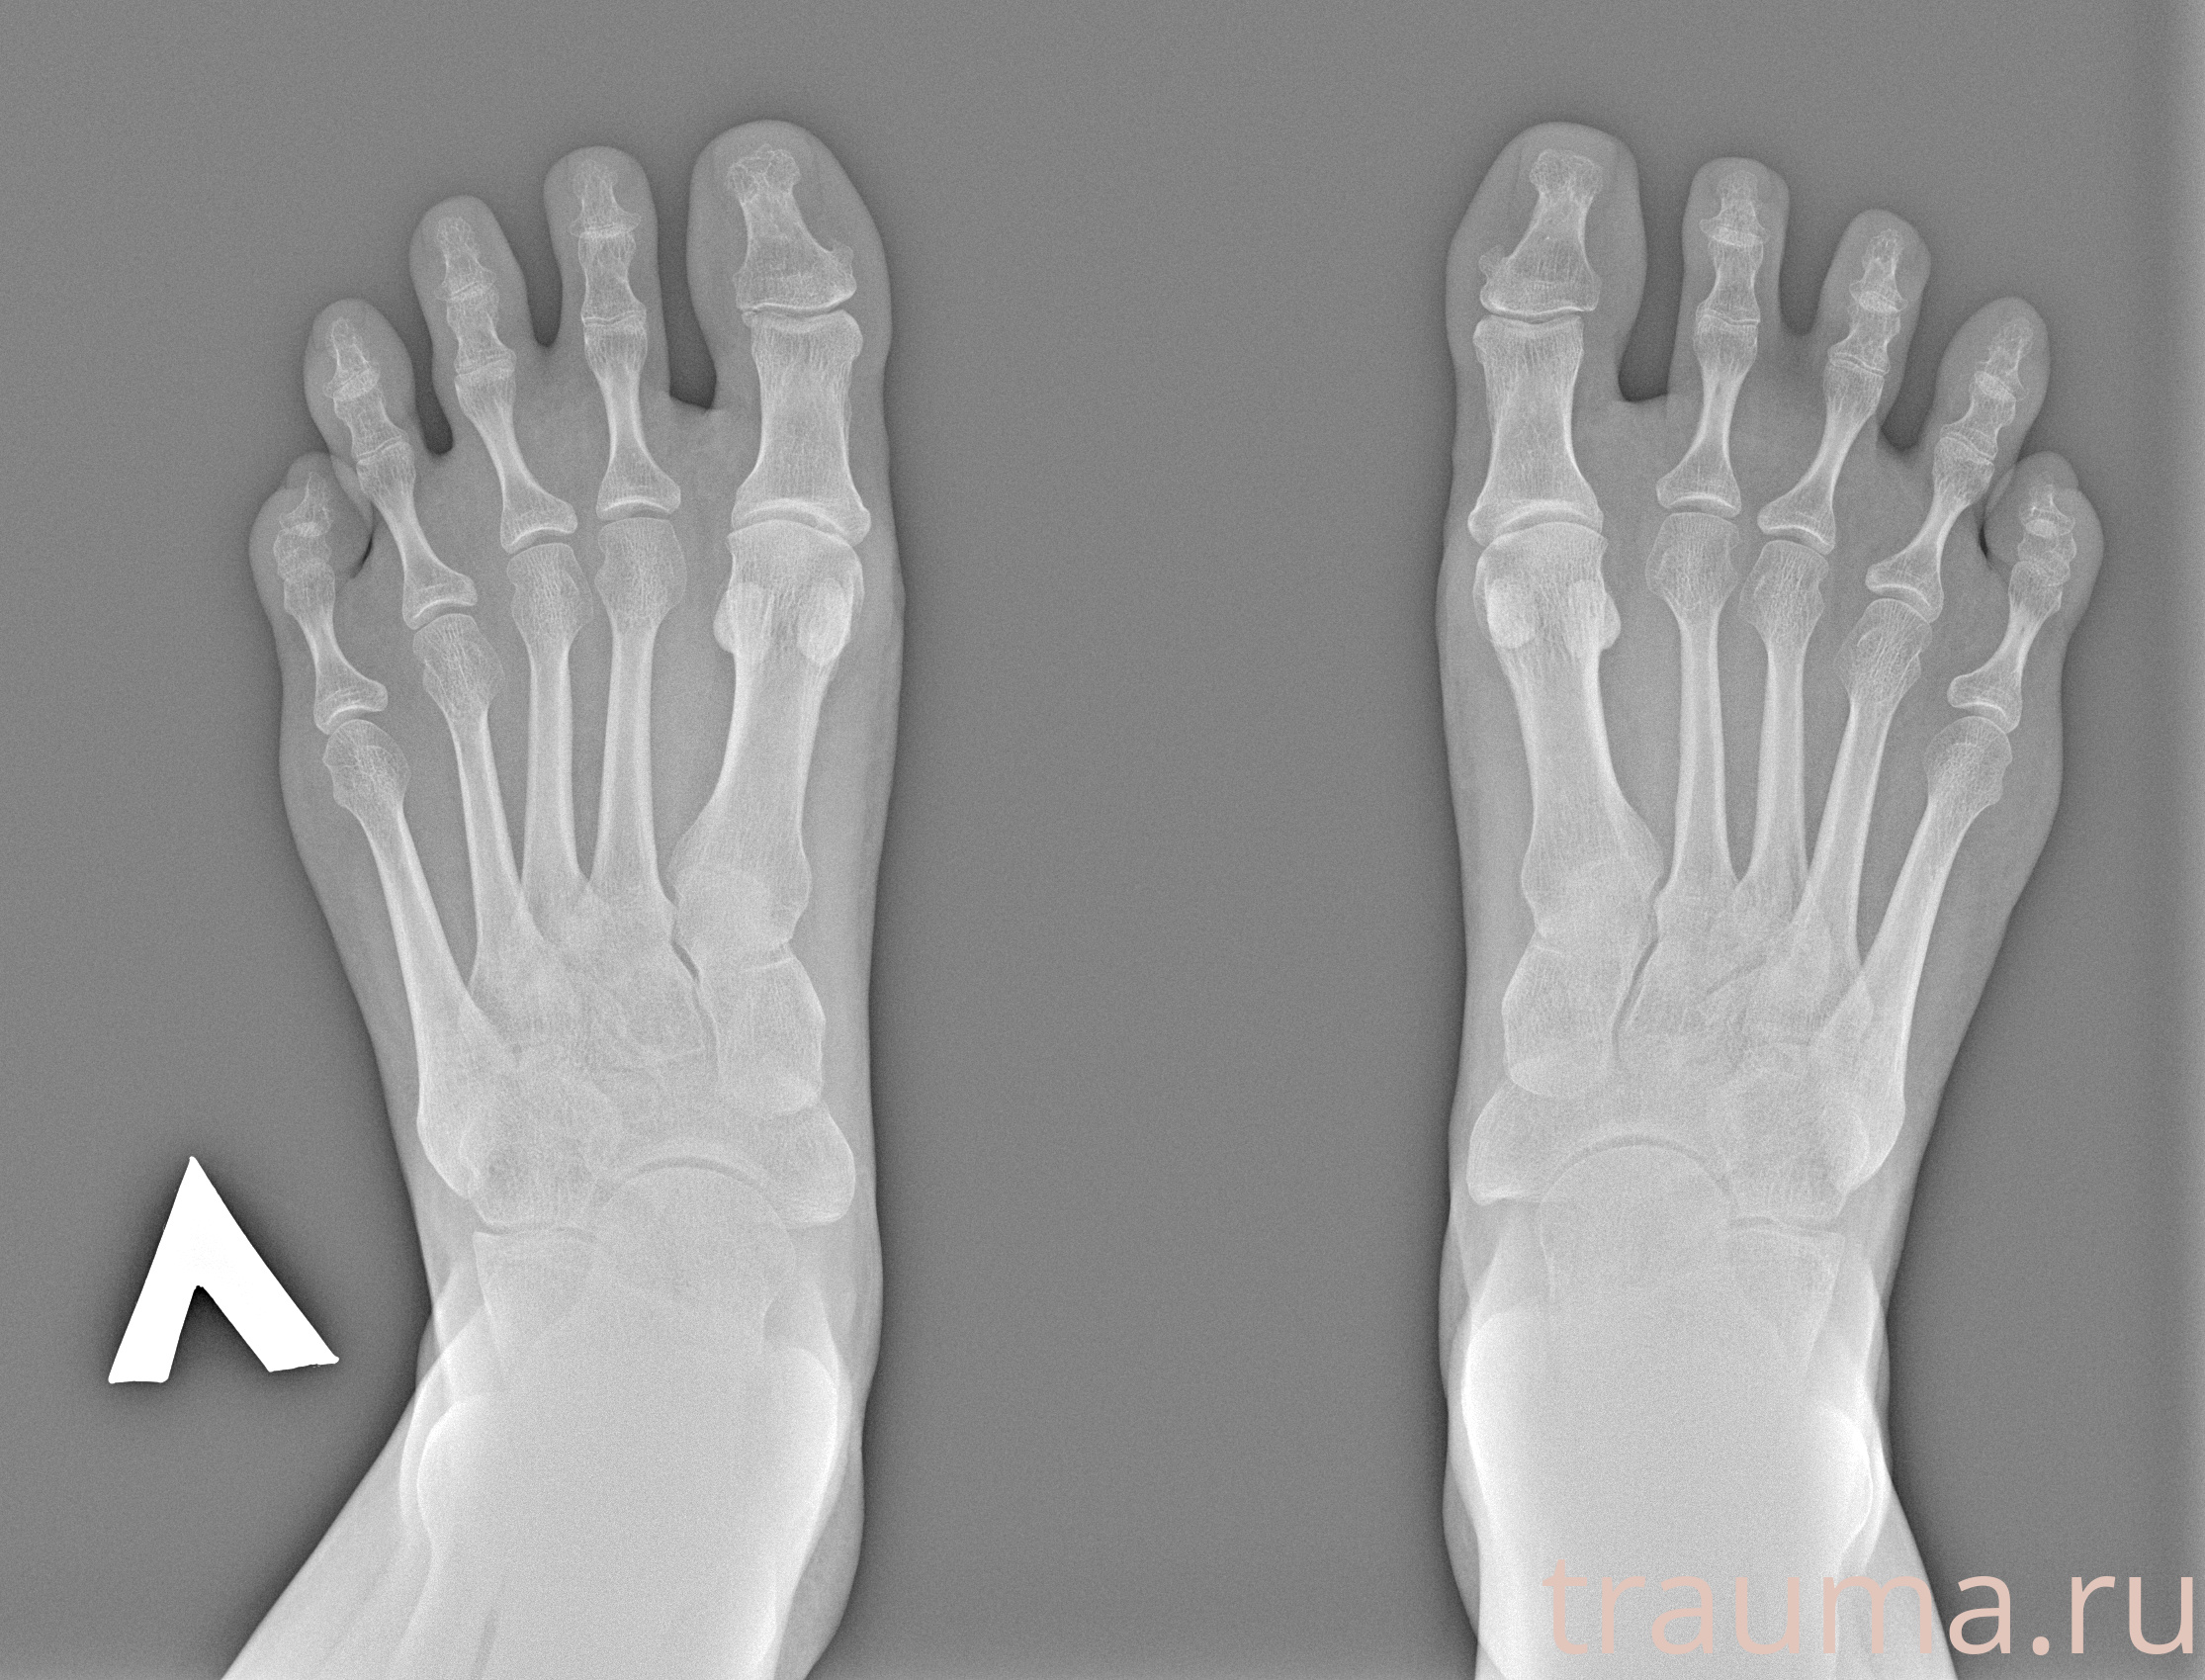

Рентгенограммы

Рентген на дому: по вашему адресу приезжает врач-рентгенолог, травматолог-ортопед с мобильным рентгеновским аппаратом, проводит диагностику травмы или заболевания, делает необходимые рентгенограммы, дает рекомендации по дальнейшему лечению. Получить качественные снимки в домашних условиях возможно благодаря уникальной методике, разработанной МосРентген Центром для института  Склифосовского